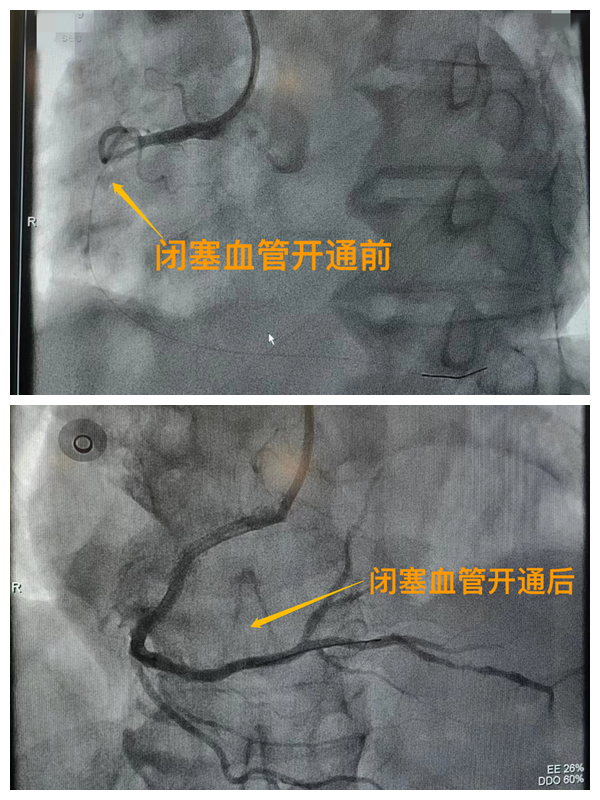

市二院胸痛中心于2021年12月23日通過(guò)中國(guó)胸痛中心認(rèn)證,成為國(guó)家級(jí)胸痛中心,先后開展了冠心病的介入診療、心律失常的心內(nèi)電生理檢查及射頻消融治療、永久起搏器植入、先天性心臟病的介入封堵及臨時(shí)起搏器植入、主動(dòng)脈內(nèi)球囊反搏治療等,完成心臟介入手術(shù)3000余例。多次創(chuàng)造從入院至行急診介入手術(shù)開通血管(入門-導(dǎo)絲通過(guò))30分鐘以內(nèi)記錄,極大保證了患者的生命安全,提高了預(yù)后質(zhì)量,挽救了眾多急性心梗患者的生命。(尹紅婭       張   靜)